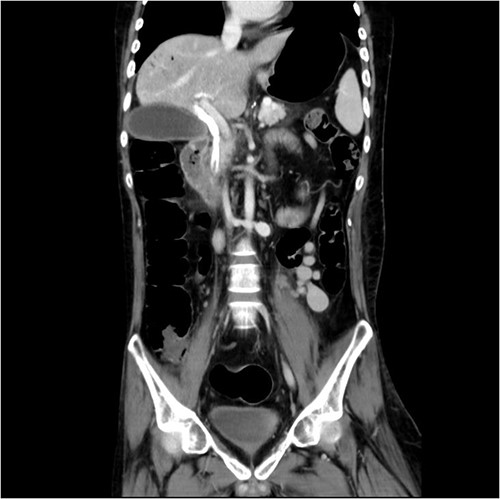

And then, a 7 French bostone scientific plastic stent was inserted over the guide wire for bile diversion. However, hemobilia was noted to be draining out from the stent right after. After reviewing the image, we realised that PVC was probably made (Fig. 3). After discussing with the general surgeon, we decided to arrange immediate surgical exploration to check for collateral damage and remove the CBD stones for cholangitis resolution. The stent was thus left inside for surgical guidance. Before the surgery, abdomen computed tomography (CT) was done and revealed retained contrast medium in the bile duct (Fig. 4) and malposition of the CBD internal stent with upper portion in the main portal vein (Fig. 5).

Malposition of the CBD internal stent with upper portion in main portal vein.

During the surgery, cholecystectomy was performed through the subcostal incision. Then the choledochoscope was inserted through the cystic duct stump to remove the stone in middle third of the CBD. Following the Kocher maneuver, we identified the internal stent penetrated through the CBD and into the portal vein at the intrapancreas level, with its tip at 1 cm above the gastroduodenal artery level. After we confirmed that no associated artery or organ injury was made, the malpositioned stent was removed by the gastroenterologist cooperatively through esophagogastroduodenoscopy. A 5 french nasogastric tube was then inserted through the cystic duct stump into distal CBD as a new stent. There was no vascular repair done and no hemorrhage or bile leakage was noticed intra-operatively under the surgeon’s surveillance.